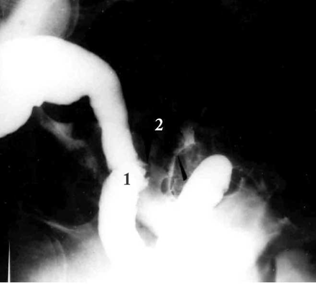

הסיבוך השני בשכיחותו הוא הנצורים, הנוצרים על רקע של דלקת הסעיפים, הנדבקים אל איברים סמוכים ומתנקבים לתוכם. נצורים אלה עלולים לחדור לעור, לכיס השתן (Colovesical fistula), לנרתיק (Colovaginal fistula) או למעי הדק. חולים אלה מספרים על הפרשת צואה וגז בשתן (פקלאוריה (Fecaluria) ופנאומטוריה (Pneumaturia)) או דרך הנרתיק. כדי לברר את מיקום הנצורים יש לבצע חוקן בריום, ציסטוגרפיה (צילום כיס השתן) או פיסטולוגרפיה (צילום הנצור). לעתים, כשהנצור צר מאוד, אפשר להדגימו רק על-ידי פיסטולוגרפיה.

בחוקן בריום אפשר להדגים פחות מ-50% מהנצורים. בצילום כליה (Pyelography) ניתן לראות עוד פחות מהנצורים, וציסטוסקופיה מראה אודם ובצקת של הרירית באזור הנצור. קולונוסקופיה (תצפית מעי גס) חשובה בחולים הללו, מכיוון שהנצורים עלולים להיגרם גם על-ידי שאת ממארת של הכרכשת, אותה יש לשלול. טומוגרפיה ממוחשבת היא בדיקה טובה להדגים נצורים בין הכרכשת לבין איברים אחרים.